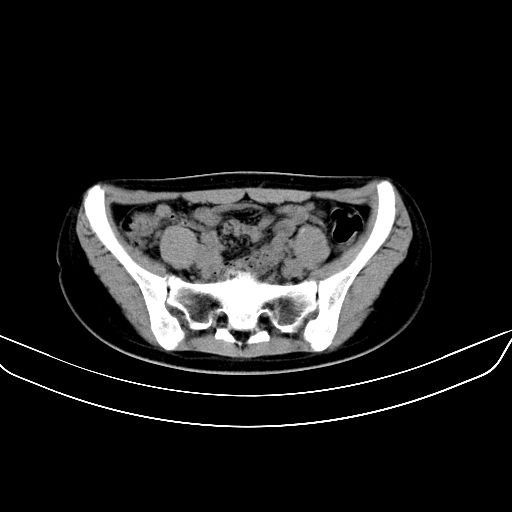

以下是引用zsl6918在2008-7-11 21:40:00的发言:[br]双侧骶髂关节骨质破坏以下三分之一为主,符合强直性脊柱炎表现

以下是引用zhangzhongshou在2008-7-11 21:41:00的发言:[br]患者是女性,hla-b27抗原(—),首先不太考虑强直性脊柱炎,建议查类风湿因子,骶髂关节改变考虑类风湿性关节炎可能性大,建议进一步检查。